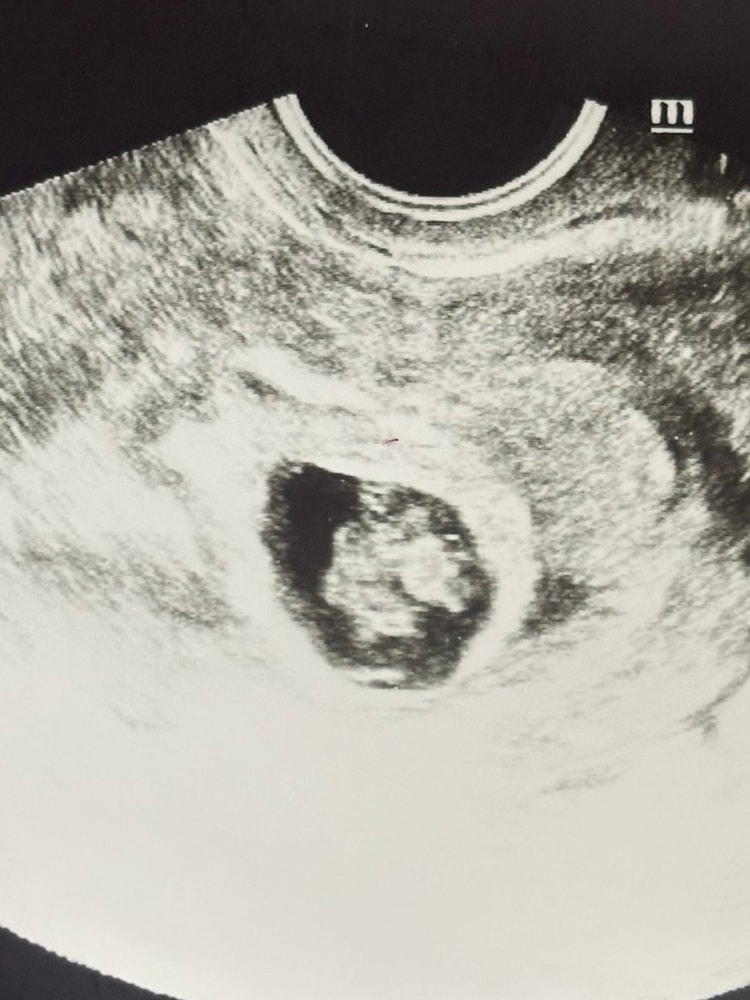

Вера , вот здесь первое узи, когда их увидели. Акушерский 5,4 недели Изображение